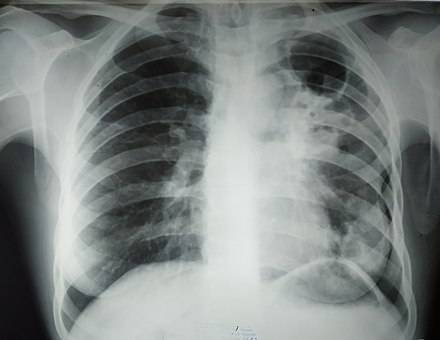

Больному назначают лабораторное и инструментальное обследование. Самый распространенный способ диагностики – туберкулезная проба Манту. Также проводятся анализ на мокроты, рентгенография легких. Результаты диаскинтеста и квантиферонового теста при туберкулезе положительные. Эффективными методами исследования являются УЗИ и флюорография. Если возникают сомнения в постановке диагноза, могут рекомендовать проведение компьютерной или магнитно-резонансной томографии.

На такой стадии туберкулез легких можно уже идентифицировать по рентгенологическому снимку, где четко просматриваются основные специфические признаки болезни – «бугорок» и творожистый некроз. При исследовании мокроты выявляется наличие микобактерий (палочек Коха).

Чтобы выявить открытый туберкулез легких, проводят различные диагностические мероприятия. Сначала врач опрашивает пациента, выясняя, когда у него появились первые признаки недомогания, какие симптомы беспокоят и др. Также он уточняет, были ли контакты с туберкулезным больным. После этого осматривает пациента, прослушивает легкие и обследует лимфатические узлы.

Одним из распространенных методов диагностики является рентгеновское обследование. Рентген рекомендуется всем тем, кто тесно контактирует с инфицированными людьми. Например, медицинские работники, которым по делу службы приходится иметь контакт с больными, более подвержены заболеванию. Поэтому они должны регулярно проходить рентгеновское обследование.